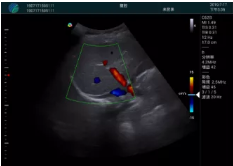

肝內(nèi)血管顯示清晰,血流敏感無外溢

2001年美國健康護(hù)理研究和質(zhì)量監(jiān)督局(AHRQ)批準(zhǔn)了一項(xiàng)關(guān)于提高患者安全性的報(bào)告,建議:在頸內(nèi)靜脈中心置管術(shù)時(shí)使用超聲引導(dǎo)。此后超聲引導(dǎo)穿刺被用于幾乎所有的急診穿刺操作,尤其是血管穿刺。

便攜超聲在急診穿刺中的應(yīng)用:

* 提高了穿刺成功率

* 減少了穿刺損傷及并發(fā)癥

* 縮短了操作時(shí)間

* 減輕了患者痛苦